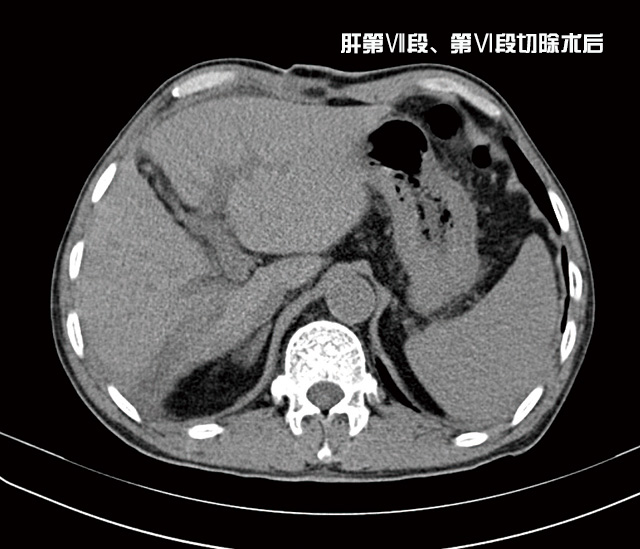

經(jīng)過(guò)充分準(zhǔn)備后,由李森主任為他成功實(shí)施了肝第Ⅶ段、第Ⅵ段切除手術(shù),術(shù)后劉大爺恢復(fù)良好,精神抖擻,日前已康復(fù)出院。